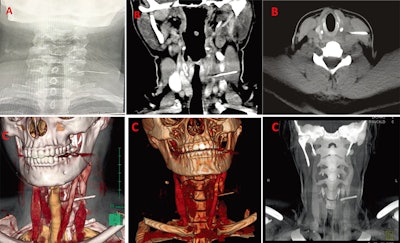

After a thorough exam and a flexible fiber-optic nasopharyngolaryngoscopy didn't reveal the foreign body in her upper aerodigestive tract, the clinicians saw a tender, nonfluctuant, diffuse swelling of about 2 x 2 cm on the left side of her neck. The x-ray showed a long, thin, smooth, and impinged foreign body, lying lateral to the esophagus. CT showed that something metallic and 3 cm in length had pierced through the woman's left internal jugular vein and the left sternocleidomastoid muscle. Doctors used 3D reconstruction and virtual endoscopy images to localize the needle and plan for the surgery, the authors wrote.

Virtual endoscopy and 3D reconstruction should be used to aid the diagnosis of airway pathology because they help clarify the location and characteristics of foreign bodies. Also, a multidisciplinary team of surgeons, radiologists, and anesthesiologists should be consulted when difficult airway management cases occur. Finally, dentists should use larger needles when available and take extra care when injecting patients, they wrote.